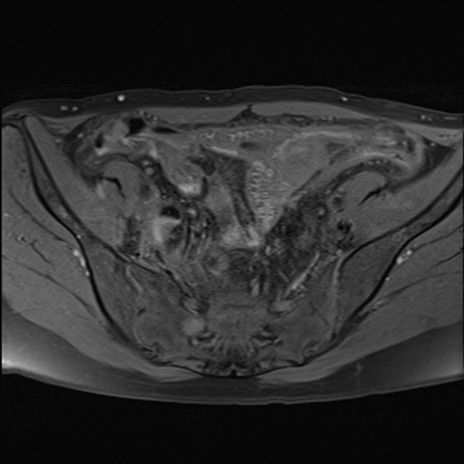

症例39 脂肪抑制T1WI(横断像)

MRI(4日後)

T1WI(横断像)